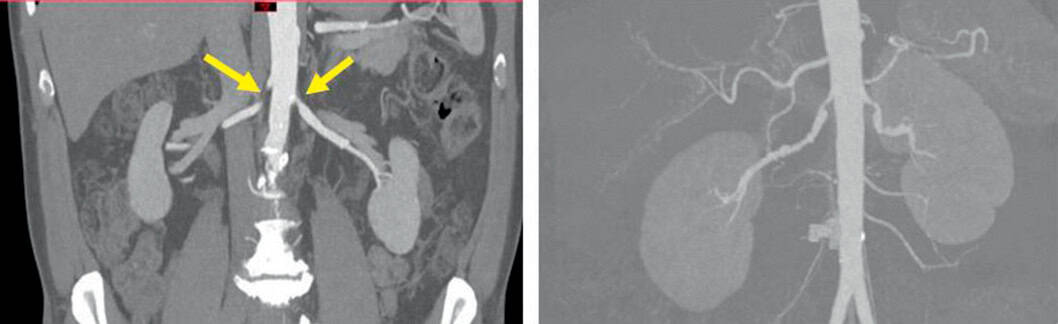

Figure 2.8. Exemples de sténoses des artères rénales.

À gauche : sténose athéromateuse post-ostiale bilatérale des artères rénales. À droite : sténoses étagées des artères rénales dans un contexte de dysplasie fibromusculaire multifocale bilatérale.

- angioscanner si le DFG est supérieur à 30 ml/mn ou en prenant des mesures de protection contre la néphrotoxicité de l’iode s’il est inférieur : mise en évidence de la sténose, visualisation des autres axes vasculaires, orientation vers l’étiologie (athérosclérose, dysplasie fibromusculaire) (fig. 2.8) ;